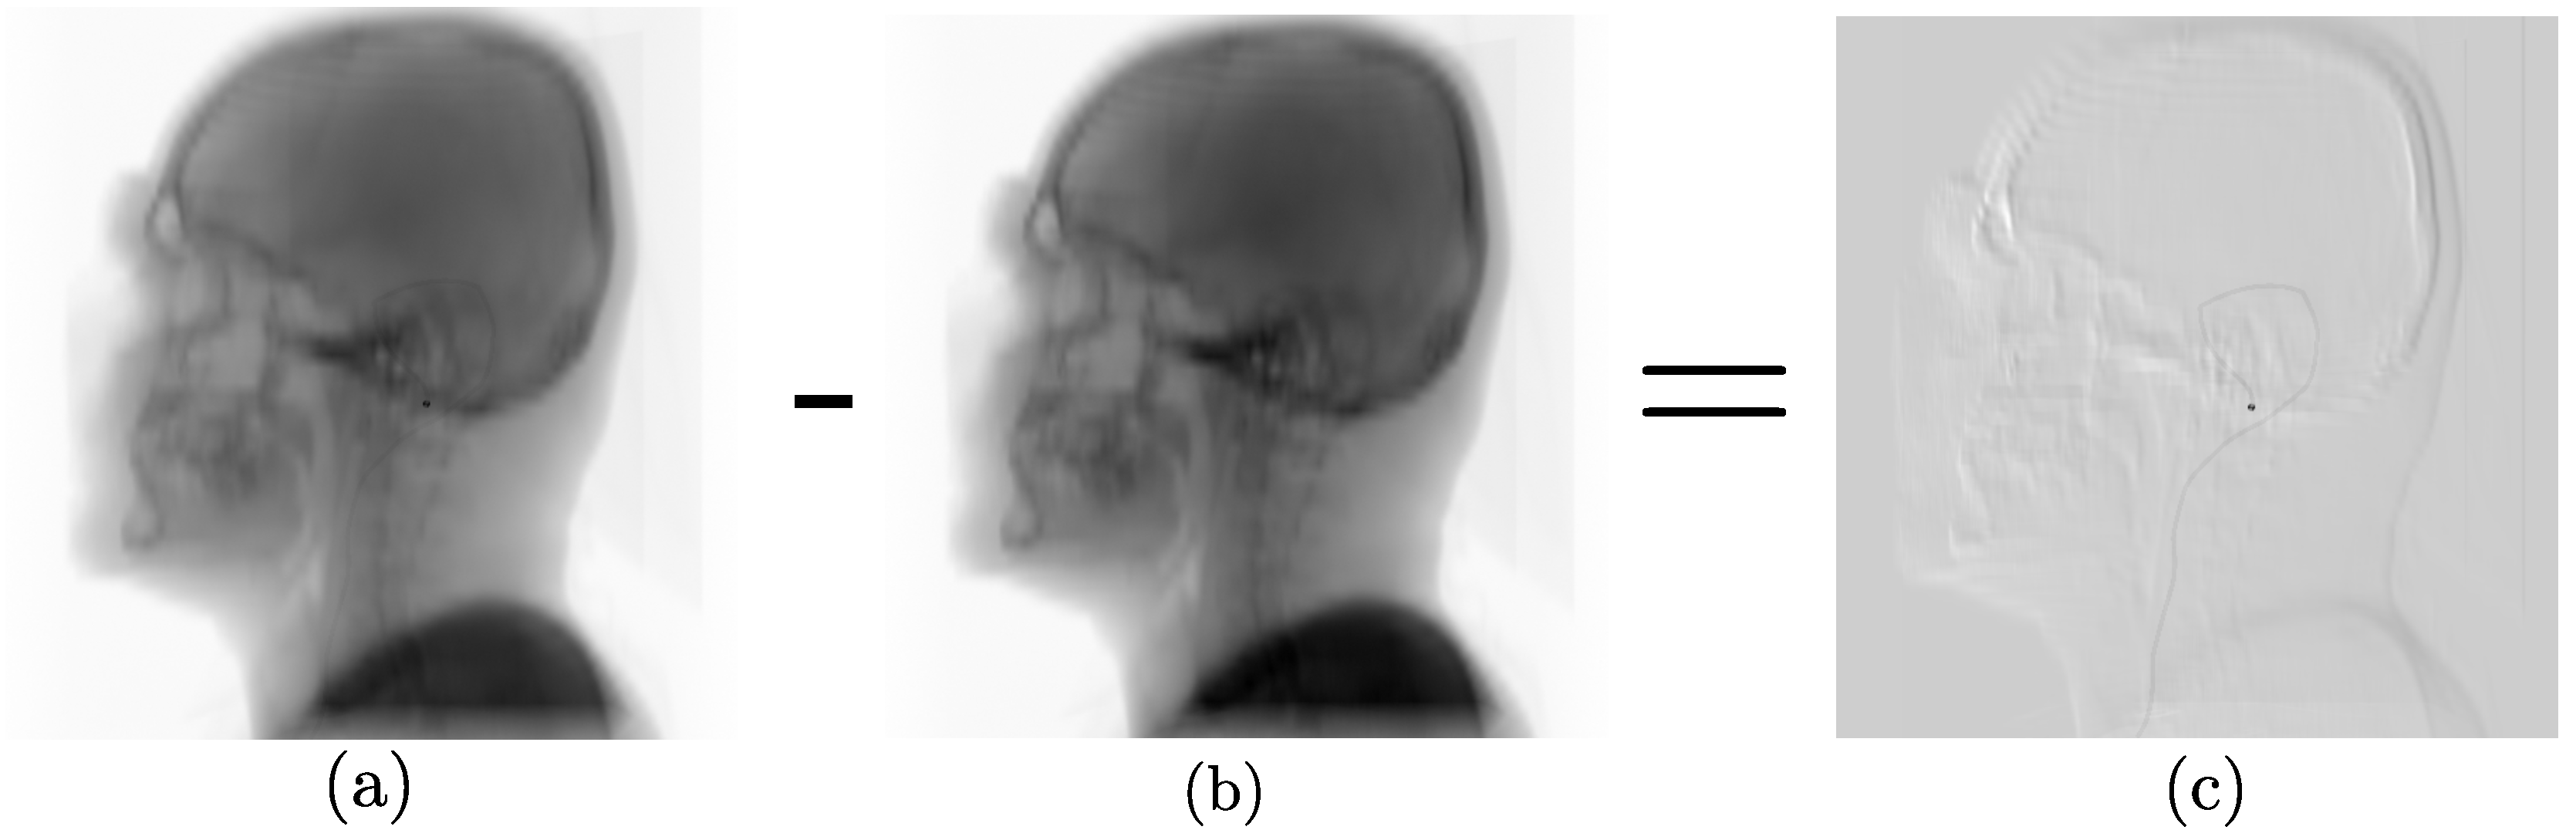

2.1. Data Synthesis